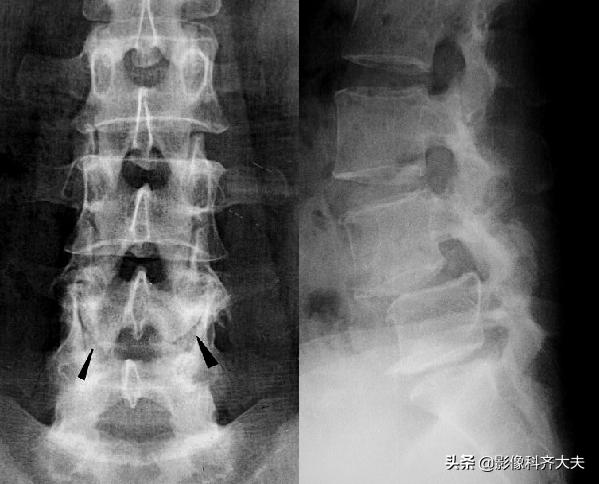

椎体压缩骨折:

病史:高处坠落;重物冲击

X线表现:椎体楔形变,前缘凹陷;前后左右径增大,间隙正常;椎体中部密度增高,小梁紊乱;椎体、椎弓常见骨折碎片;脊椎后突、成角、移位。

X线平片:

可单个发生或多个椎体同时发生。

受累椎体可出现压缩骨折、楔形压缩骨折并椎体前缘游离骨块、前上缘与上位椎体下缘套叠骨折、纵行骨折等形态。

除形态改变外椎体松质小梁骨折嵌入,密度相对较高,表现为椎体面下0.1~1cm或在椎体中部的致密带状影,边缘较模糊。

胸12及腰2楔状变形,胸12椎体前缘可见碎骨片

椎体压缩骨折常合并上下关节突、横突、椎弓根及棘突骨折,一般X线平片正侧位可观察清楚。